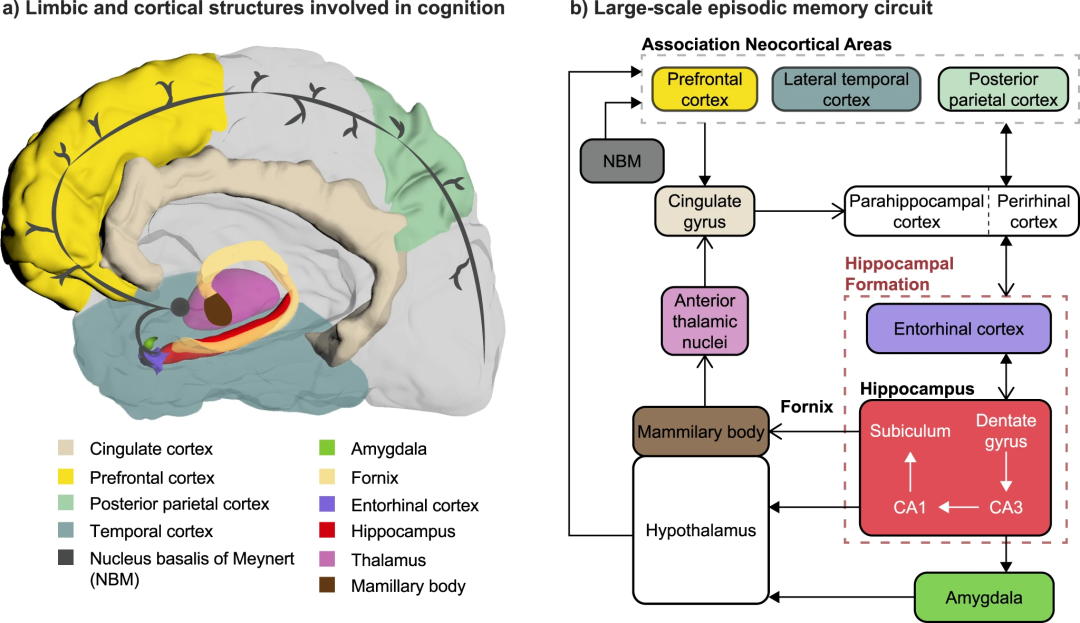

图3.认知障碍和痴呆可能的神经调节策略。a. 与认知有关的边缘和皮层结构,特别是情景记忆。这些结构是一个共同的大规模大脑网络的一部分。b. 这些结构之间的连接示意图,包括海马内回路(红色虚线框),Papez的原始回路(开放箭头),以及它们之间的附加连接(填充箭头)。NBM对新皮层区域提供广泛的胆碱能神经支配,因此作为认知的神经调节靶点而受到关注。穹窿一直是AD患者的主要慢性DBS靶点。